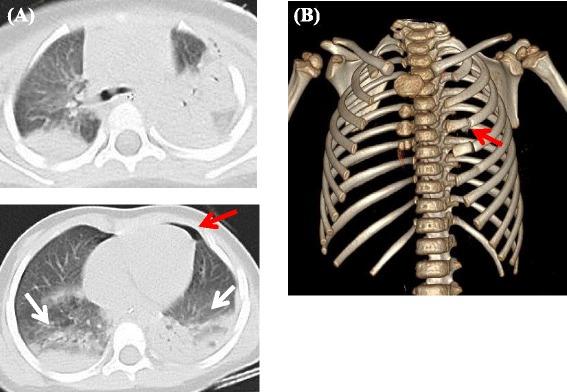

Comparison of two pediatric flail chest cases.

Flail chest is a rare complication in pediatric patients with blunt chest trauma. There is no general consensus on which treatment is most appropriate for flail chest in pediatric patients, although it has been reported that surgical fixation is associated with beneficial outcomes for flail chest in adults. The present report described two pediatric cases of flail chest, which was rare in pediatric blunt trauma. In small children, functional residual capacity is smaller, and the thorax is pliable due to high thoracic compliance. Therefore, it is only advisable to select intubation and mechanical ventilation treatment. Likewise, in pediatric flail chest, the available evidence does not suggest that ventilator management protocols should be adopted routinely, and the treatment for pediatric flail chest was not established completely. There were not huge different between the described patients, including injury severity and ventilation setting. However, one had a relapse of flail chest after extubation and chest taping was required, while the other patient's condition was stable after decannulation. As described above, it is difficult to predict a recurrence of flail chest in pediatric patients even if treatment goes well. Therefore, T-piece trial should be considered prior to extubation.